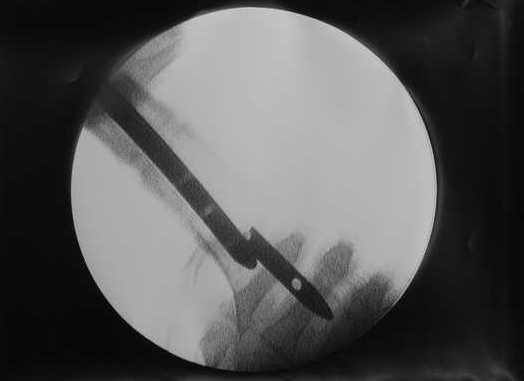

В приложении пример, как их использовали после остеотомии бедра по поводу сросшегося с вальгусом перелома, чтобы не дать гвоздю уйти во внутренний мыщелок.

Да, действительно красивый клинический пример: виден вальгус до операции и последующая коррекция углового смещения на "полярах". Я так понимаю, что в вашей клинике есть возможность использовать различные фиксаторы. Почему не использовали DFN? Спицы какие используете? Киршнера или Илизаровские? С виду очень тонкие...